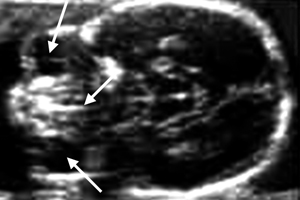

Εικόνα 1. Απεικόνιση τομών στα τρία κύρια επίπεδα.

Στην 20η εβδομάδα, η οργανογένεση του εμβρύου έχει ολοκληρωθεί και ακολουθεί η ωρίμανση των δομών του που διαγράφονται με ευκρίνεια. Αυτό, σε συνδυασμό με το μέγεθος του εμβρύου, που του επιτρέπει να αλλάζει συχνά θέσεις, καθιστούν την εξέταση του 2ου τριμήνου (18-24εβδ.) τη σημαντικότερη για την επιβεβαίωση της αρτιμέλειας του εμβρύου, της ανακάλυψης τυχόν δομικών ανωμαλιών και την ανίχνευση υπερηχογραφικών δεικτών σχετικών με χρωμοσωμικές ανωμαλίες. Ο μαιευτήρας, κατά την εξέταση, θα πρέπει να είναι συγκεντρωμένος και να ακολουθεί συγκεκριμένο πρωτόκολλο, ώστε να μην του διαφύγουν σημαντικές παρατηρήσεις.

Οι βασικές απεικονίσεις του εγκεφάλου:(1,2,6,19)

- Διαθαλαμικό επίπεδο (1).

- Διακοιλιακό επίπεδο (2).

- Διαπαρεγκεφαλιδικό επίπεδο (3).

Α. Διαθαλαμική απεικόνιση